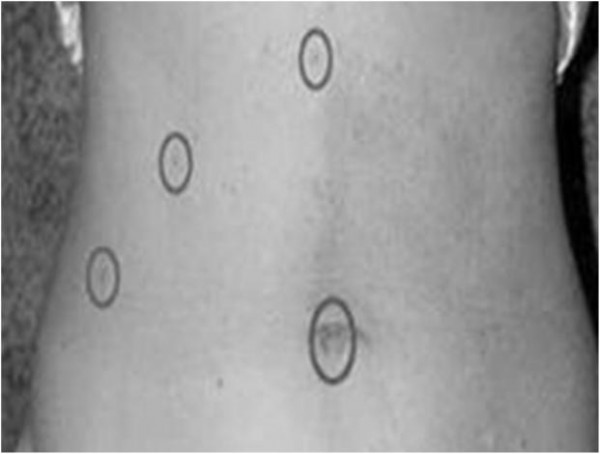

그러나 복강경 담낭 절제술은 개복하지 않고, 복부에 3-4개의 투관침을 삽입하고, 복강내시경을 통해 담낭을 절제하는 수술이다.

개복을 하지 않기 때문에 약 1cm 크기의 투관침 부위의 반흔만 남겨서 수술 상처가 거의 남지 않으며, 수술 후 심한 통증이나 장

유착이 드물고, 수술 후 2-3일째에 퇴원이 가능하며, 정상적인 사회생활로의 복귀도 그만큼 빠르다.

![]()

(개복 담낭 절제술) (복강경 담낭 절제술)